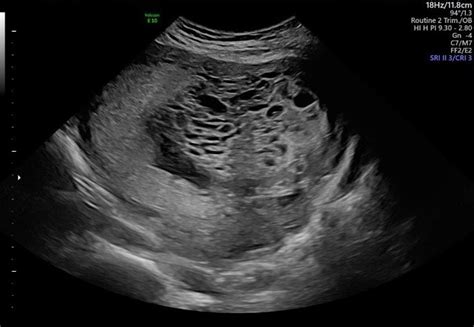

Molar Pregnancy Sonogram

A sonogram, or ultrasound, is the primary imaging technique used to visualize the uterus. When a technician or doctor performs a Molar Pregnancy Sonogram, they are looking for specific visual patterns that distinguish a healthy pregnancy from a molar one. Because the condition involves rapid, disorganized tissue growth, the images produced are quite distinct from those of a healthy developing embryo.

One of the most characteristic signs identified during the sonogram is the presence of what sonographers call a "snowstorm" pattern. This is caused by the multiple fluid-filled cysts that develop within the placental tissue. In a healthy pregnancy, the ultrasound would show a gestational sac, a yolk sac, and eventually a clearly defined embryo or fetus with a beating heart. In contrast, the molar scan often shows a complex mass of echoes and cystic spaces filling the uterine cavity.